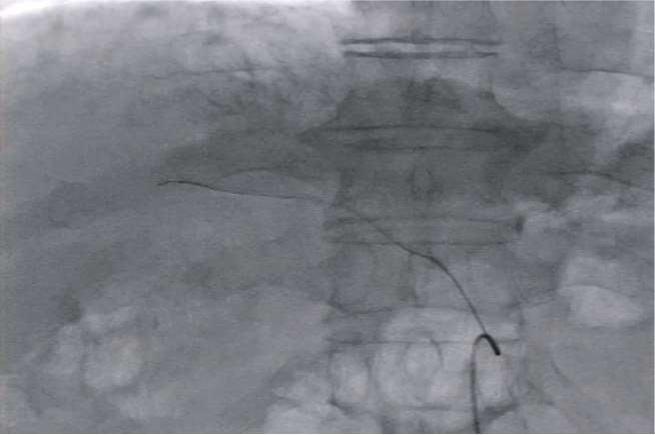

Tri-axial system with steerable microcatheter